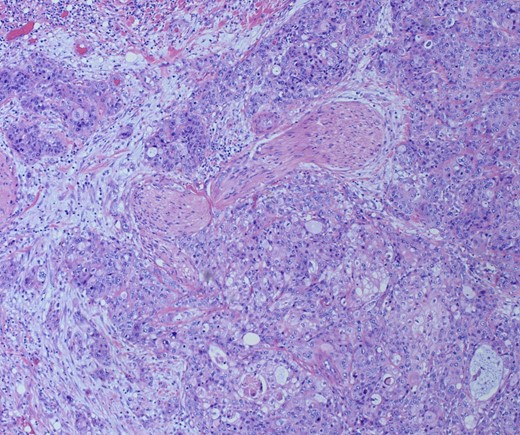

She underwent an open pylorus-preserving pancreatoduodenectomy with segmental superior mesenteric vein resection with primary reconstruction (ISGPS Type 3) without complication. Final pathology demonstrated a 3.6-cm poorly differentiated adenosquamous carcinoma with SMV invasion into the intima (Fig. 2), 1 of 24 regional lymph nodes with metastatic carcinoma, lymphovascular and perineural invasion (Fig. 3), and an 85% squamous differentiation (Fig. 4). There was a partial pathologic response (College of American Pathologist Grade 2) within the primary tumor and involved lymph node tumor [7]. There was noted to be tumor extension within 1 mm of the superior mesenteric artery margin (Fig. 5) (R1 status) with negative additional margins. She recovered without complications and was discharged home on the fourth post-operative day. Repeat staging CT imaging demonstrated no evident disease. She was initiated on adjuvant systemic therapy.

Adenosqumous carcinoma with both components (adeno and squamous) A19 Cytokeratin 7 immunostain, highlighting the adenocarcinoma, and p40 immunostain, highlighting the squamous carcinoma component